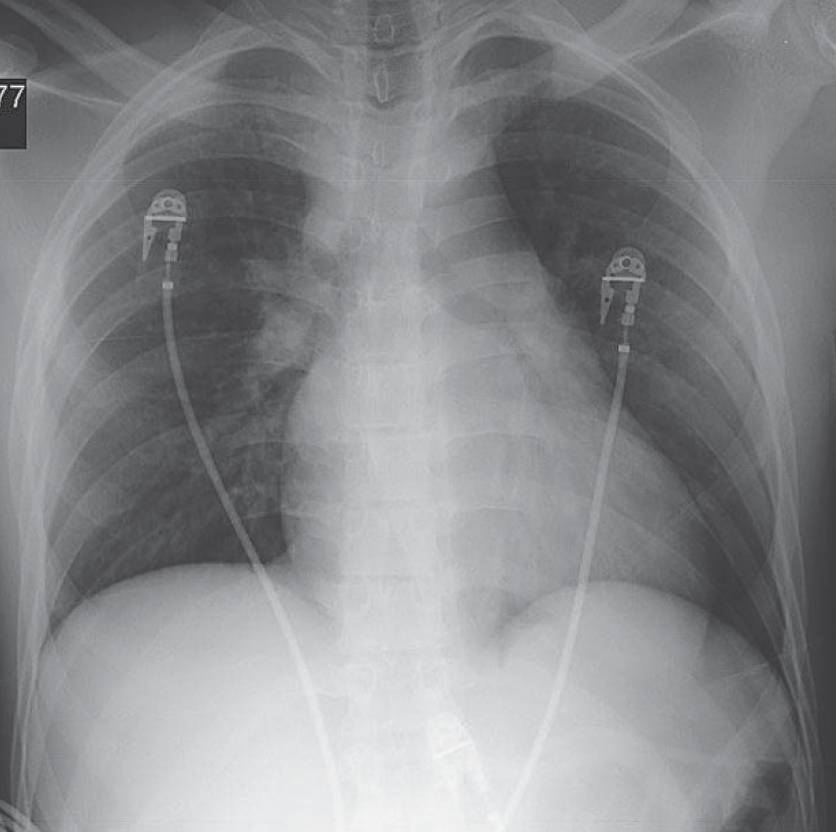

19-year-old Man After a Motor Vehicle Collision Post category:Spot Diagnosis Post published:November 15, 2025 Share on Facebook Share on X (Twitter) Share on Pinterest Share on Email Share on Reddit 19-year-old man after a motor vehicle collision is imaged in the trauma suite 19-year-old man after a motor vehicle collision is imaged in the trauma suite. What’s the diagnosis ? FULL CASE AND ANSWER Share on Facebook Share on X (Twitter) Share on Pinterest Share on Email Share on Reddit Read more articles Previous PostA 62-year-old Man with Periocular Purpura You Might Also Like A 6-year-old Boy with Several Hours of Vomiting and Dyspnea March 20, 2022 Erythematous and Tender Abdominal Lesion April 19, 2022 Nonpruritic, Well-Circumscribed, Scale-Covered, Erythematous Plaques on Palms and Soles November 3, 2021